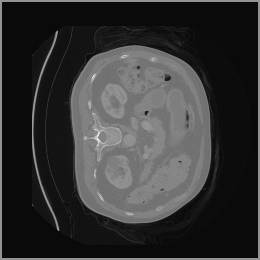

The motivation for this work arises from the need to address these limitations in the synthesis of 3D medical images. Current techniques do not produce high-resolution 3D images that preserve spatial coherence and capture the full complexity of medical data, as shown in Figure 2, 5. The development of advanced 3D generative models tailored specifically for medical imaging could not only improve the quality of synthetic medical images but also help alleviate data scarcity, enhance privacy protection, reduce computational requirement and ultimately advance the use of deep learning in healthcare applications.

To demonstrate the advantages of 3D semantic image synthesis over 2D semantic semantic image synthesis, we conducted a detailed comparison with the SegGuidedDiff [26] model. SegGuidedDiff generates medical images based on 2D semantic maps, producing individual 2D slices that are later stacked to form a 3D image. However, this approach has limitations in capturing spatial continuity and coherence across slices, which is critical for representing the spatial structure of 3D medical images. As a result, inconsistencies often arise between different slices, particularly in preserving anatomical structures across the coronal and sagittal planes. The generated images exhibit varying levels of denoising, resulting in differences in brightness and sharpness across the images. This inconsistency in denoising can lead to noticeable variations in visual quality, where some regions appear clearer and others less distinct.

As shown in Figure 5, the generated slices exhibit high consistency across adjacent slices. The anatomical structures and semantic patterns are smoothly and coherently preserved between slices, indicating that our model is capable of generating 3D-consistent synthetic images rather than isolated 2D slices.